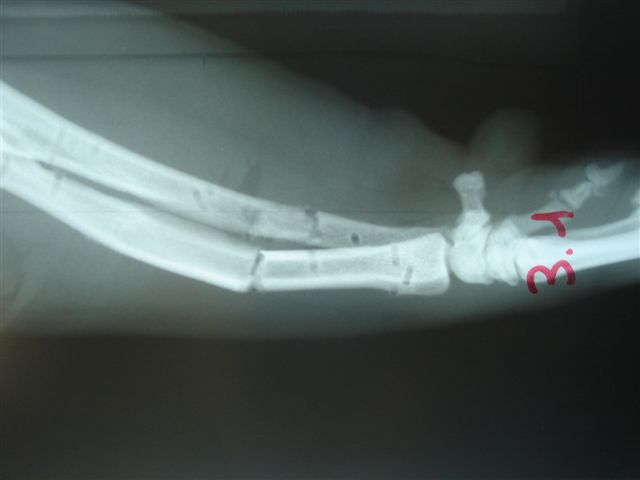

Fijación Externa en IVOT

Fijación Externa

IX CURSO BASICO DE FIJACION EXTERNA.

Casos prácticos alumnos.